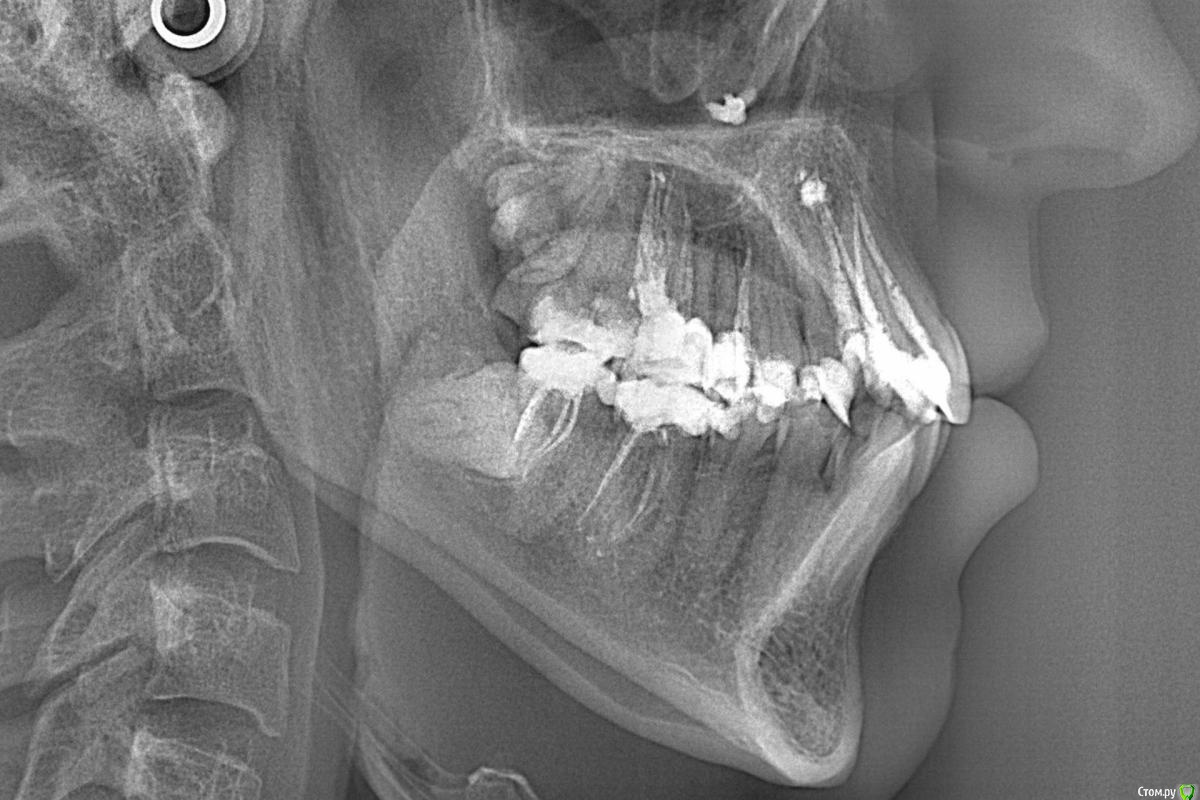

Didi Опубликовано 9 февраля, 2016 Автор Поделиться Опубликовано 9 февраля, 2016 Был на приёме у ортодонта.Ортодонт сказал что зубы двигать нельзя вообще, потому что кости вокруг зубов очень мало.Посмотрите пожалуйста, он прав?Это корни видны через десну? Ссылка на комментарий

Didi Опубликовано 12 февраля, 2016 Автор Поделиться Опубликовано 12 февраля, 2016 (изменено) сходите к другому ортодонтуА этот разве не прав? Он говорит что при передвижении зубов кости становиться меньше вокруг зубов чем были, а у меня говорит кости и так почти нету, плюс зубы крупные.Корни передних нижних зубов частично оголены.Передние корни видны сквозь дёсны. Он не прав? Я правильно вас понимаю?Проблем не будет, можно двигать? Изменено 12 февраля, 2016 пользователем Didi Ссылка на комментарий

Didi Опубликовано 17 февраля, 2016 Автор Поделиться Опубликовано 17 февраля, 2016 Как бы вам так обьяснить- конечно той инфо что вы предоставили мало - но - все решаемо- вопрос только в понимании проблеммы доктором и его знаниях.Какую ещё инфу прислать? (в первом сообщении темы прикреплены фото рта и панорамный снимок) То что сказал доктор вызывает сомнение к его компетенции? Ссылка на комментарий

m.d.n Опубликовано 20 февраля, 2016 Поделиться Опубликовано 20 февраля, 2016 НУУ я бы хотел увидеть нормальные фото , кт, модели- анализ трг надо провести , опг посмотреть, и тогда панировать лечение. Если ваш доктор чего то незнает или неумеет это незначит что так нельзя делать. Ищите другого доктора. Ссылка на комментарий

Didi Опубликовано 1 марта, 2016 Автор Поделиться Опубликовано 1 марта, 2016 (изменено) НУУ я бы хотел увидеть нормальные фото Покажите примеры таких фото пожалуйста кт 3D КТ https://yadi.sk/d/cUlOzEOFp4fLkПароль BierVlad49 анализ трг надо провести http://forum.stom.ru/uploads/monthly_02_2016/post-8062-0-13613500-1455035250.jpg опг посмотреть http://forum.stom.ru/uploads/monthly_02_2016/post-8062-0-47018700-1455097096.jpg и тогда панировать лечениеВышеприведённой информации будет достаточно, или нужно что-то ещё? многопетлевая техника- ищите того кто владеет Она решает вопрос недостатка кости? Изменено 1 марта, 2016 пользователем Didi Ссылка на комментарий